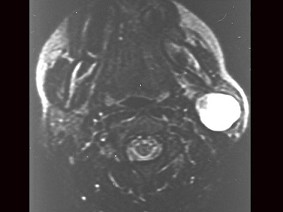

女性,30岁,右侧腮腺无痛性包块5个月,无面瘫,触诊肿块质韧,表面光滑。大小约6×8厘米,B超示腮腺浅叶实性肿块 ,均质,包膜完整。患者相片及影像资料见下图。

8.患者应该诊断为  (    )

9.患者的最佳手术方式是  (    )

正确答案:8.B;9.B;10.A